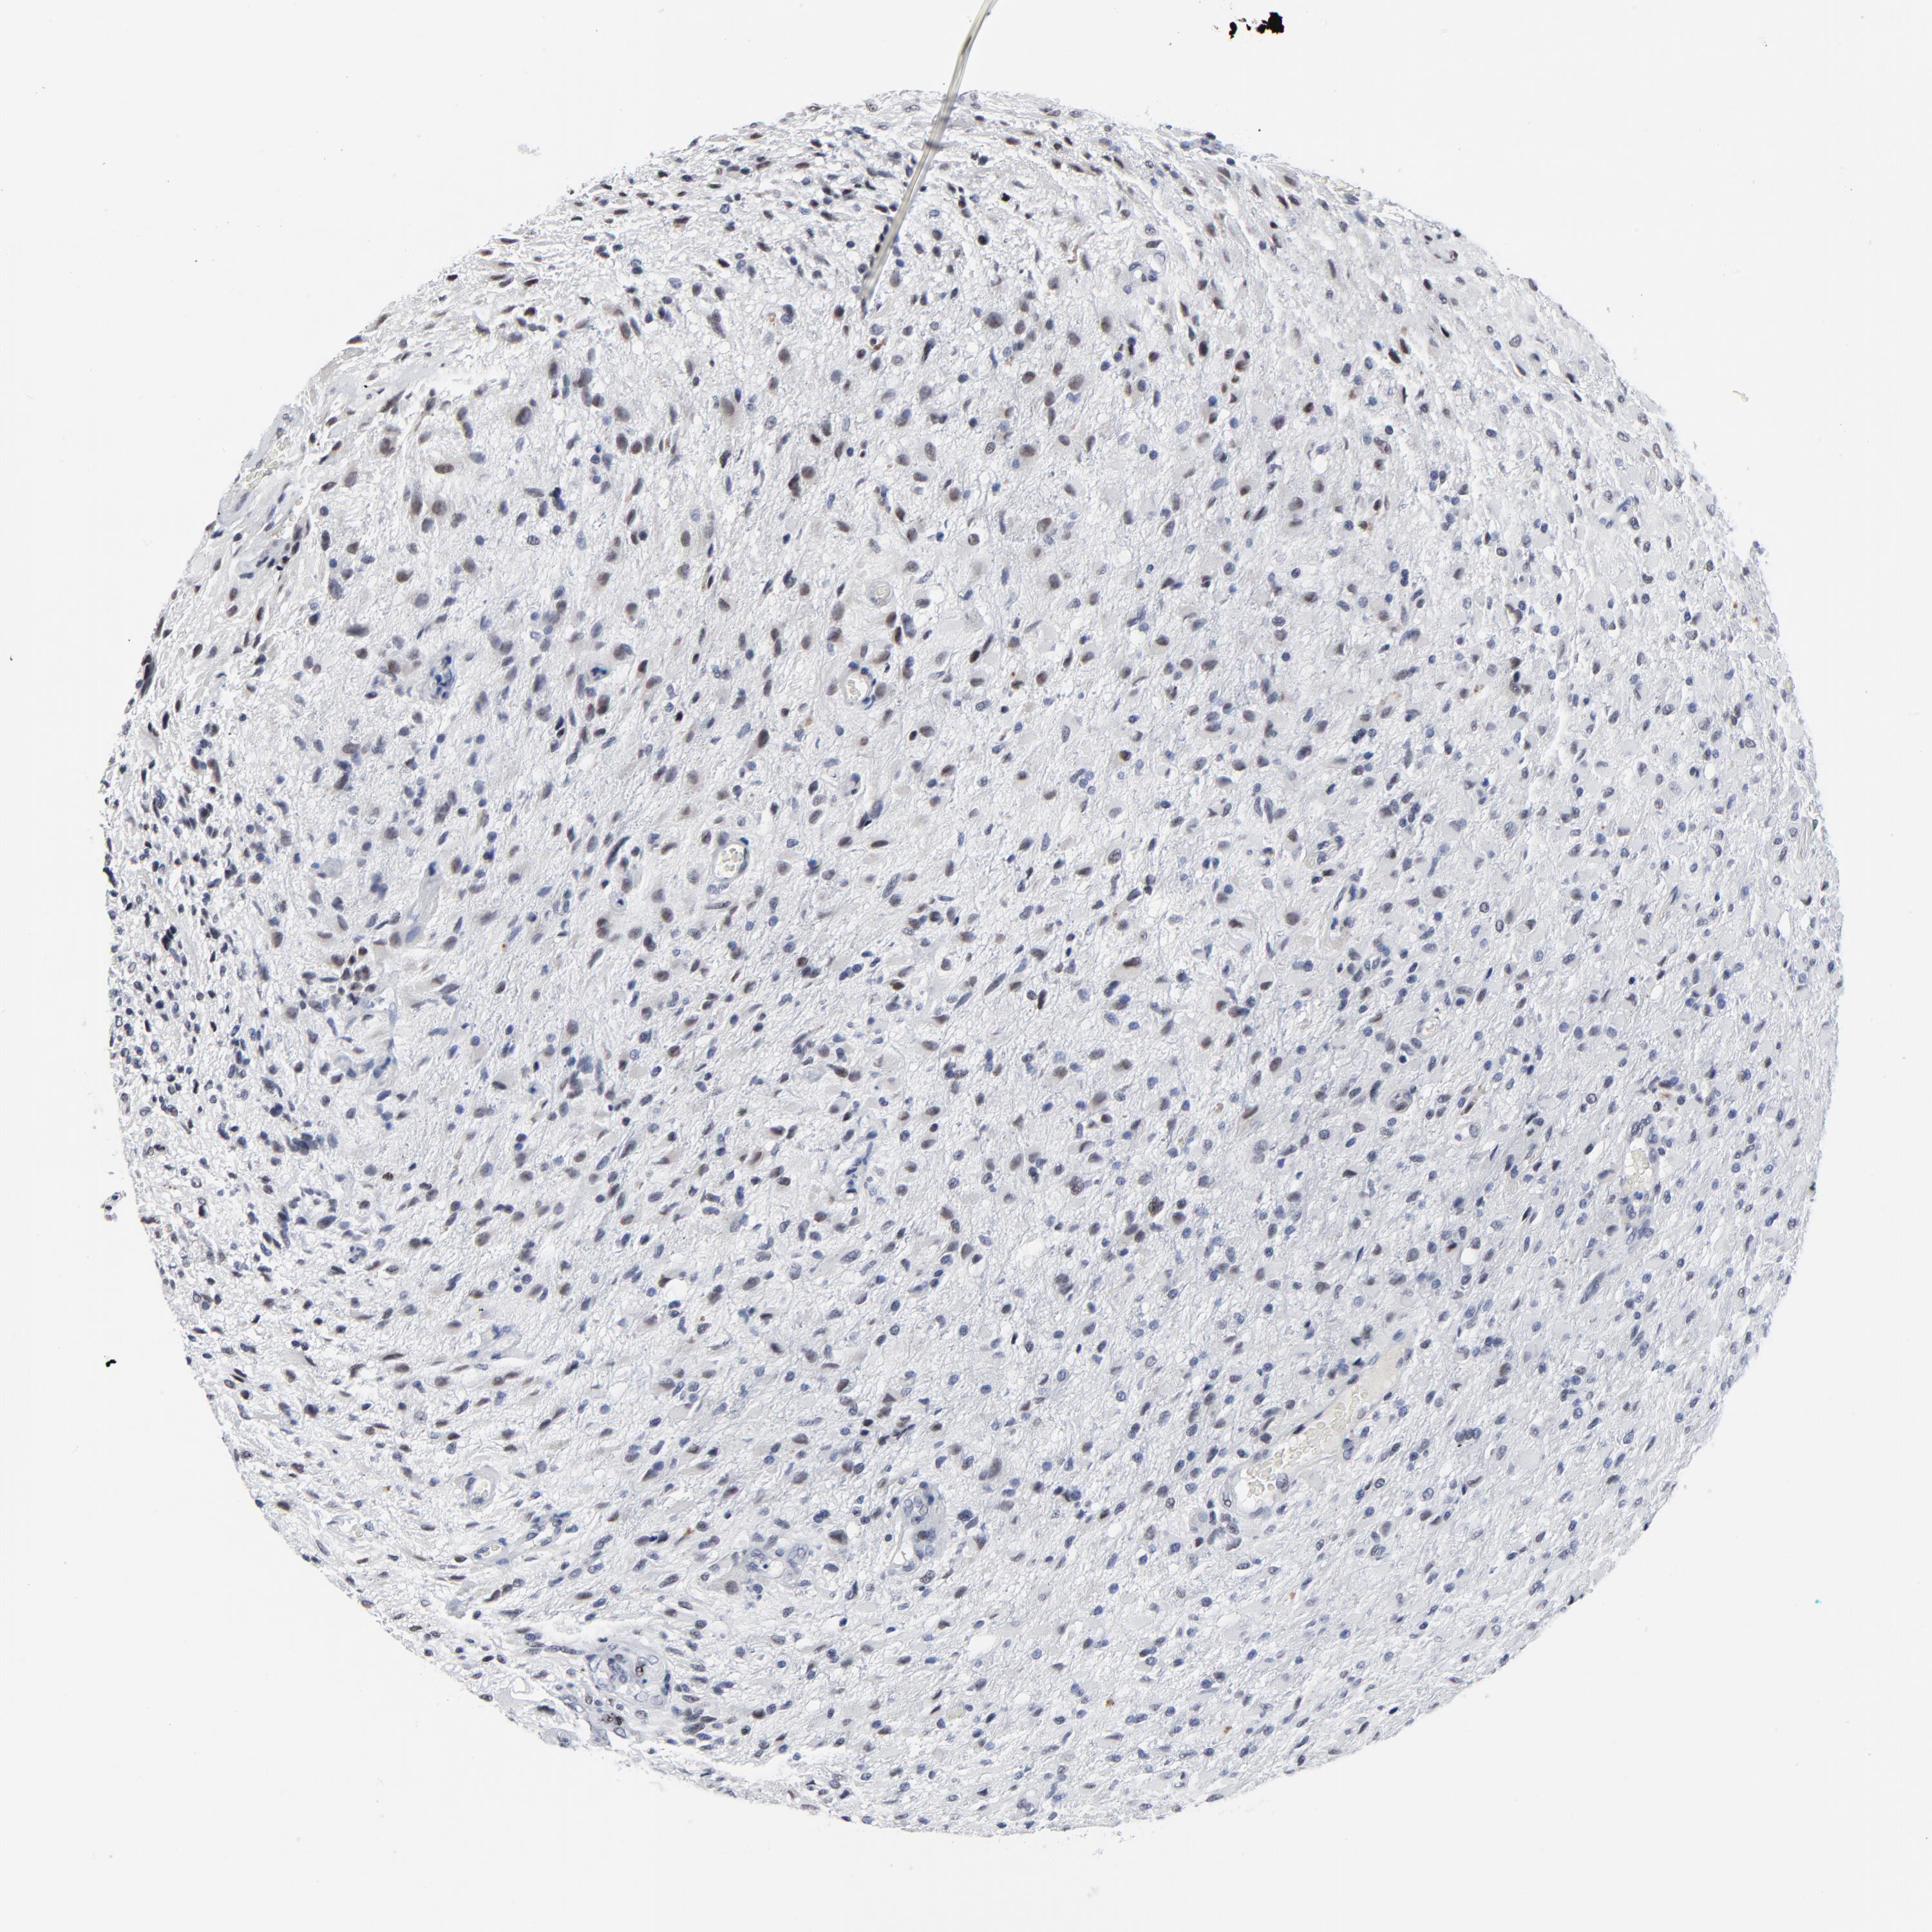

GLIOMA - Protein expressioni

A mouse-over function shows sample information and annotation data. Click on an image to view it in a full screen mode. Samples can be filtered based on level of antibody staining by selecting one or several of the following categories: high, medium, low and not detected. The assay and annotation is described here.

Note that samples used for immunohistochemistry by the Human Protein Atlas do not correspond to samples in the TCGA dataset.

Antibody stainingi

Antibody staining in the annotated cell types in the current human tissue is reported as not detected, low, medium, or high, based on conventional immunohistochemistry profiling in selected tissues. This score is based on the combination of the staining intensity and fraction of stained cells.

Each image is clickable and will lead to virtual microscopy that enables deeper exploration of all samples and also displays staining intensity scores, fraction scores and subcellular localization as well as patient and tissue information for each sample.

Antibody HPA003145

Staining

High

Medium

Low

Not detected

Intensity

Strong

Moderate

Weak

Negative

Quantity

>75%

75%-25%

<25%

None

Location

Nuclear

Cytoplasmic/membranous

Cytoplasmic/membranous,nuclear

Glioma, malignant, High grade

Glioma, malignant, Low grade